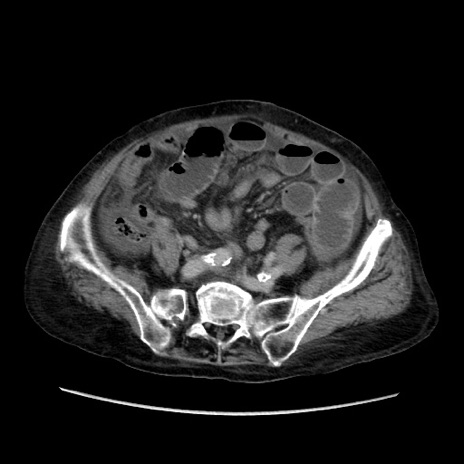

症例31(横断像)

【症例】80歳代 女性

【主訴】腹部膨満感

【現病歴】他院にて肝硬変にてフォロー中。1週間前から便秘、腹部膨満感、臍部腫瘤あり受診となる。

【既往歴】肝硬変

【身体所見】腹部膨隆あり、皮膚変化なし、疼痛なし。

【データ】WBC 4600、CRP 0.25